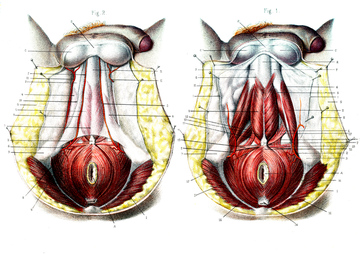

会陰 ( えいん )とは、 解剖学 において、狭義では 外陰部 と 肛門 の間、広義では左右の 大腿 と 臀部 で囲まれる 骨盤 の出口全体をさす。 恥骨結合 と左右の 坐骨結節 、 尾骨 を結ぶ菱形部となる。会陰と残尿感の解消には、 一体どのような関係性があるのでしょうか。 男性は蟻の門渡りを押すことで残尿感を解消できるのか? 排尿を終えた直後なのに「まだ膀胱内に尿が残っているような気がする、 なんだかスッキリしない」という不快感を覚える 男性の陰部のかゆみの原因として考えられる疾患とは? 男性の陰部にかゆみの症状があるとき、大まかな原因としては「性感染症」「皮膚疾患」の2つの場合が考えられます。 かゆみのある性感染症としては「性器ヘルペス・尖圭コンジローマ・梅毒」などがあり、どれも性行為により感染する可能性があります。 性器ヘルペスでは、陰部に水膨れができ

会陰部 広義の会陰の定義 (会陰部も参照) 前方の陰丘、外側の大腿内側面、後方の殿溝と殿間裂の上縁に挟まれた菱形の領域 (M) 狭義の会陰の定義 男性の場合尿道と会陰の間、女性の場合膣と肛門の間を指す (KH237) WordNet the general region between the anus and the男性の会陰は前後径5~6センチメートル、女性では2~3センチメートルである。 この部分の皮膚の正中線には色素に富んだ会陰縫線 (ほうせん)があり、男性では陰嚢縫線に続く。 会陰部皮下には脂肪組織、平滑筋線維が多く存在し、その深部には横紋筋からなる会陰筋層がある。 骨盤腔 (こう)を上方からみると、骨盤下口を会陰筋が筋膜、腱膜 (けんまく)とともに会陰部のヘルニアについて情報をまとめました。 ヘルニア治療辞典 男性と女性では、起こる場所が異なると言われていますが、女性の方がかかる率が高くなっています。 恐らく、女性は妊娠や出産などがあるため、会陰部が大きく収縮することが原因の1つではないかと考えられます。

アンティークの人体解剖図 男性会陰部 19世紀のベクターアート素材や画像を多数ご用意 Istock

男性の会陰部神経血管 の写真素材 画像素材 Image

男性会陰部解剖学 Buy 会陰解剖学 会陰解剖学 会陰解剖 Product On Alibaba Com

男性骨盤内臓器 会陰部の浅筋膜 の写真素材 画像素材 Image 1505